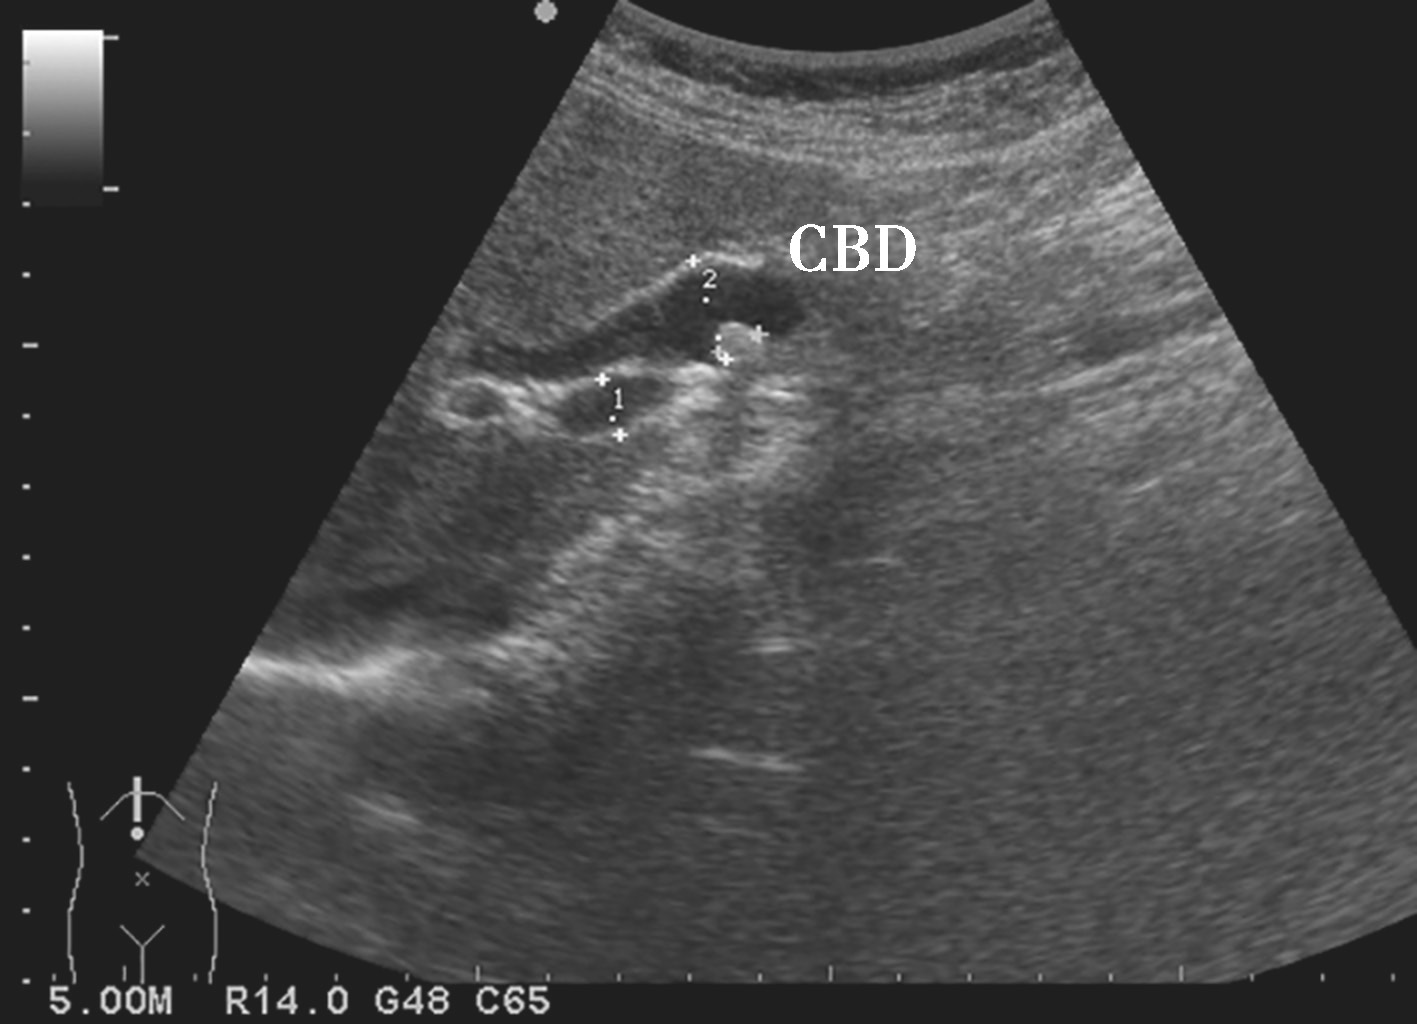

1)胆管腔内存在伴有声影的恒定团状强回声(图2-6-4),个别呈中等或低回声(图2-6-5)。

图2-6-4 肝外胆管强回声结石灰阶超声图像

图2-6-5 肝外胆管中等回声结石灰阶超声图像

CBD:胆总管